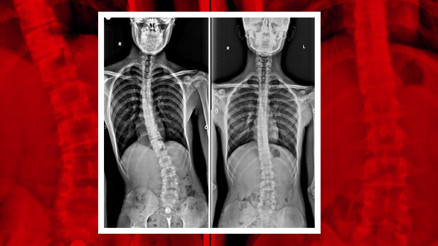

#Michael BallackSakarya’nın Adapazarı ilçesinde yaşayan 16 yaşındaki Aziz Koray Diş, geçirdiği bisiklet kazası sonrası vücudundaki eğriliğin arttığını fark edince durumu ailesiyle paylaştı. Birçok özel hastane gezen ancak teşhis konulamayan genç, tam umudunu kaybetmişken sağlığına Sakarya Eğitim ve Araştırma Hastanesi'nde kavuştu.

#SakaryaSakarya’nın Adapazarı ilçesinde yaşayan 16 yaşındaki Aziz Koray Diş, geçirdiği bisiklet kazası sonrası vücudundaki eğriliğin arttığını fark edince durumu ailesiyle paylaştı. Birçok özel hastane gezen ancak teşhis konulamayan genç, tam umudunu kaybetmişken sağlığına Sakarya Eğitim ve Araştırma Hastanesi'nde kavuştu.